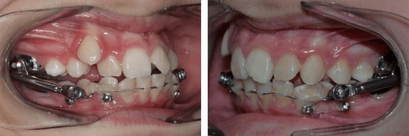

9

Q

A

Herbst appliance